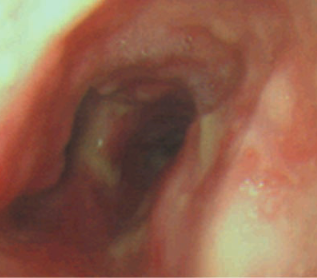

Tracheobronchopathia osteochondroplastica

trachéobronchopathie ostéochondroplastique (TOCP)

- Calcifications et epaississements nodulaires

- Trachée distale et bronches souches proximales

- Epargne la zone postérieure

- Pathologie bénigne qui peut faire un peu de toux ou hémoptysie (les nodules se frottent entre eux et saignent)

Tracheobronchopathia Osteochondroplastica